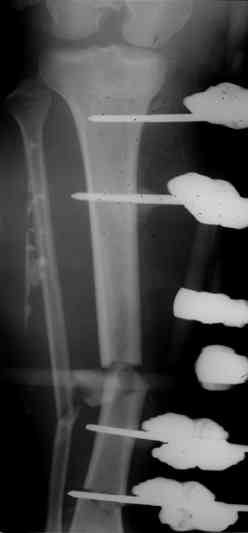

Если у Вас возникнут какие-то сомнения, то возможно наложение гибридного циркулярного-монолатерального дистракционного аппарата на левое бедро и выполнение остеотомии в в/3 бедра. Почему монолатеральный гибридный аппарат, а не аппарат Илизарова? Эта конструкция гораздо легче переносится пациентами, в ней гораздо удобнее проводить местное лечение ран.

Больной 19 ти лет, пострадал в результате ДТП, пассажир мотоцикла. Получил открытый оскольчатый перелом н/3 левой бедренной кости 3a тип по Гастилло-Андерсену. При поступлении ПХО ран, фиксация стержневым аппаратом наружной фиксации. Лечение больного осложнилось развитием анаэробной флегмоны левого бедра. Лампасные разрезы, неоднократные некрэктомии, некротизировался участок диафиза левой бедренной кости на протяжении 15 см. Произведена резекция. 20.05.10- демонтаж АНФ, остеоситез левой бедренной кости гибридным циркулярно-монолатеральным стержневым дистракционным аппаратом наружной фиксации, остетомия левой бедренной кости в в/3. Сейчас начата дистракция в аппарате, проводится подготовка ран к аутодермопастике.